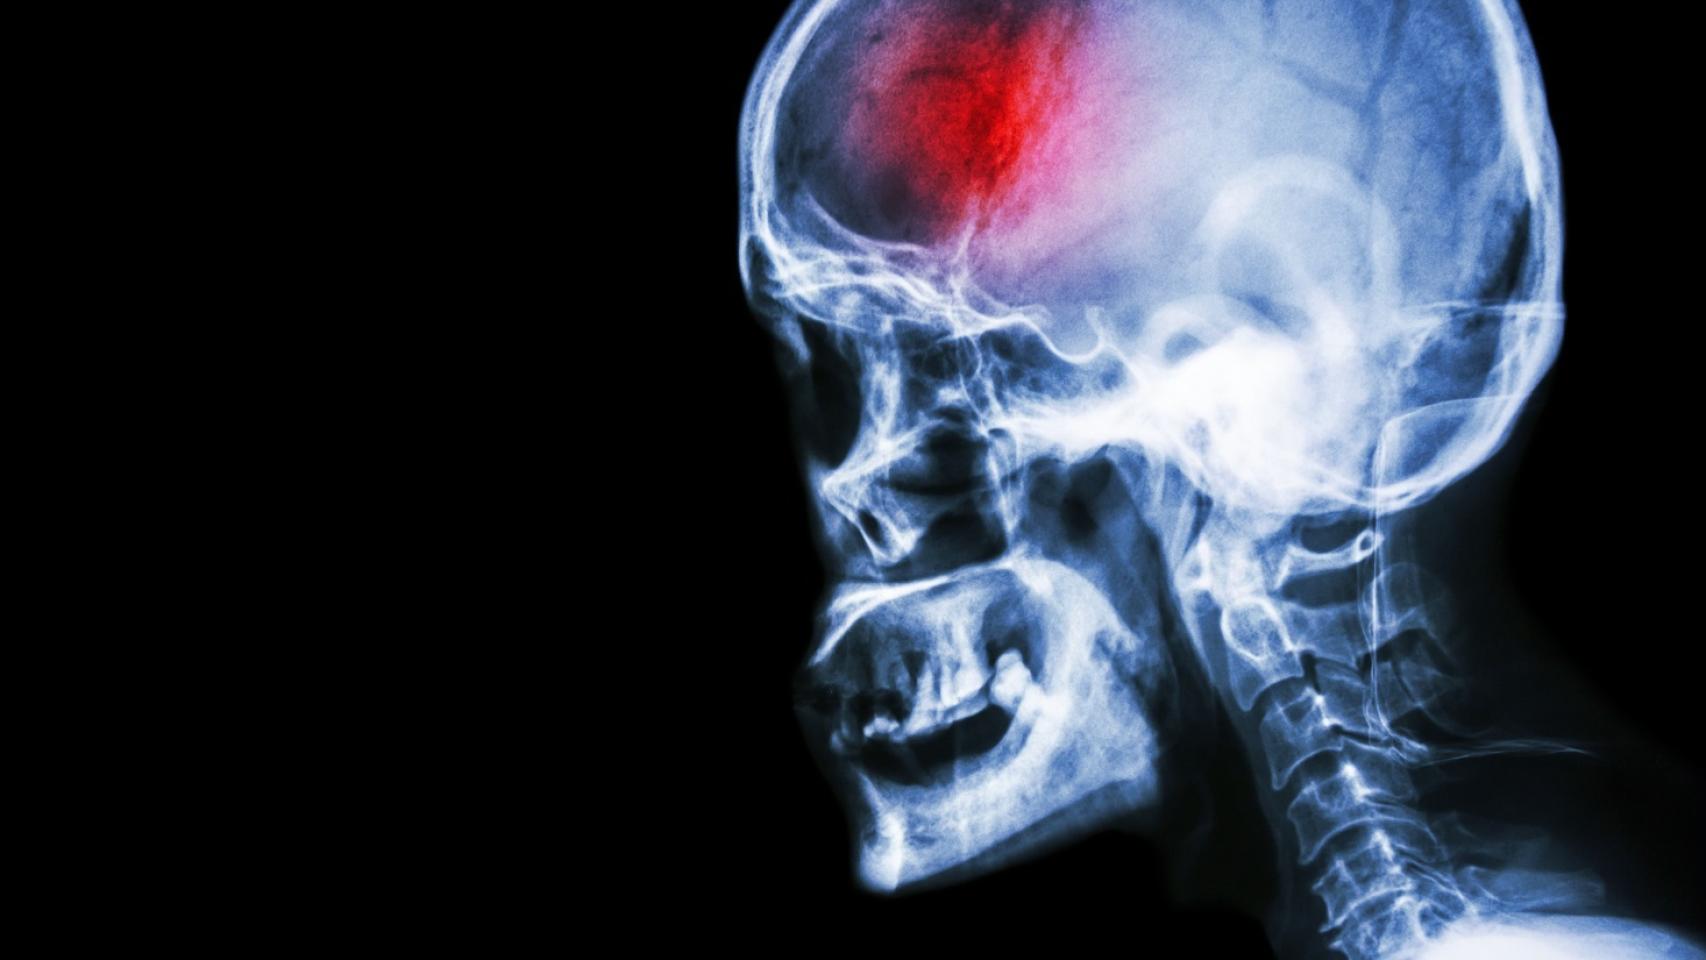

Entre las enfermedades vasculares con mayor incidencia, tanto en Málaga como en España, se encuentra el ictus. El accidente cerebrovascular se produce por el estrechamiento de las principales arterias que abastecen de sangre al cerebro.

En Málaga, la incidencia es de 200 casos por cada 100.000 habitantes al año y una prevalencia de 8 casos por 1.000 habitantes. Esto supone que al año en Málaga sufren un ictus unas 3.000 personas.

En concreto, en la Unidad de Ictus del Hospital Universitario Virgen de la Victoria de Málaga desde 2021 han tratado 5.000 pacientes y este año ya han atendido a 500 pacientes. Por lo que de media al mes atienden a un centenar de pacientes y a un millar al año.